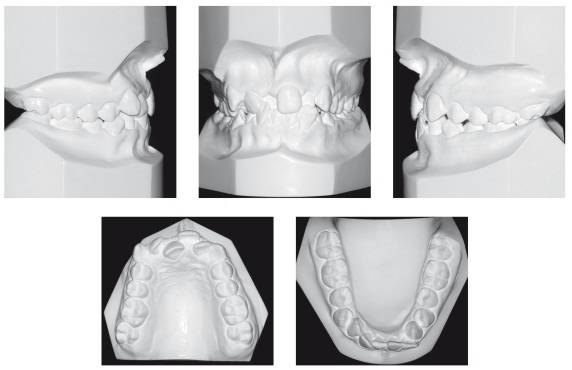

取模型:医生先在口中取阴模,然后用石膏灌注模型,还原牙列形态。石膏模型可以使医生直观地视察牙齿排列状况,从而制定矫治方案。同时,石膏模型也是进行治疗前后对比的重要依据。最新科技可以让我们采用口内扫描仪代替常规取模,或者在取模后通过模型扫描,获得数字化模型。

石膏模型(上)与数字化模型(下)